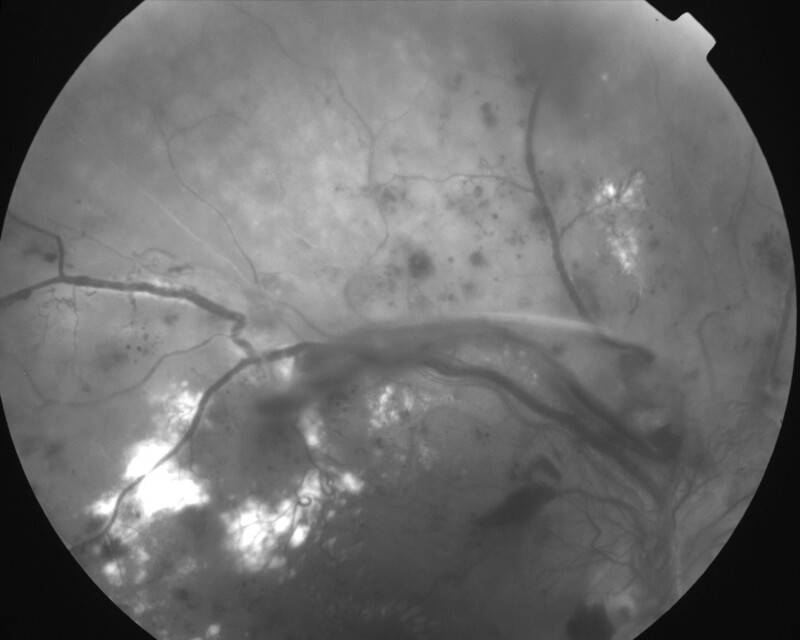

RETINOPATHIE DIABETIQUE PROLIFERANTE